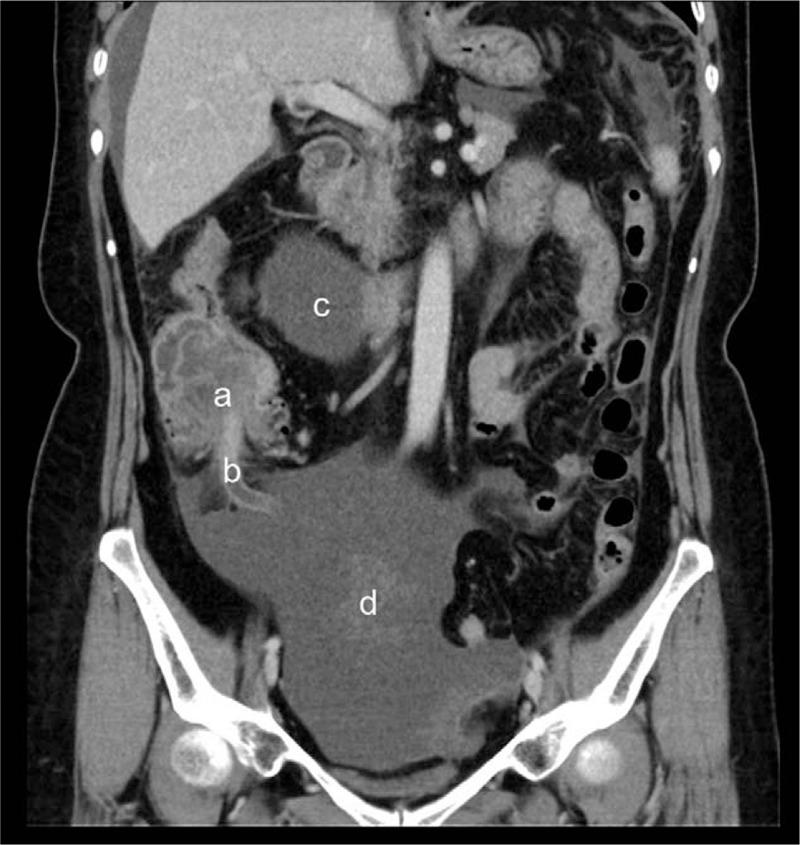

A 60-year-old woman who complained of severe pain around the navel with nausea and vomiting for a week was admitted on November 28, 2017. There were multiple watery stools and abdominal pain was worsened over the prior week.

She was diagnosed by abdominal computed tomography, current medical history, and abdominal signs. Her initial diagnosis was acute abdomen, intussusceptions, and intestinal obstruction. The final diagnosis was MAC, which was based on postoperative pathology.